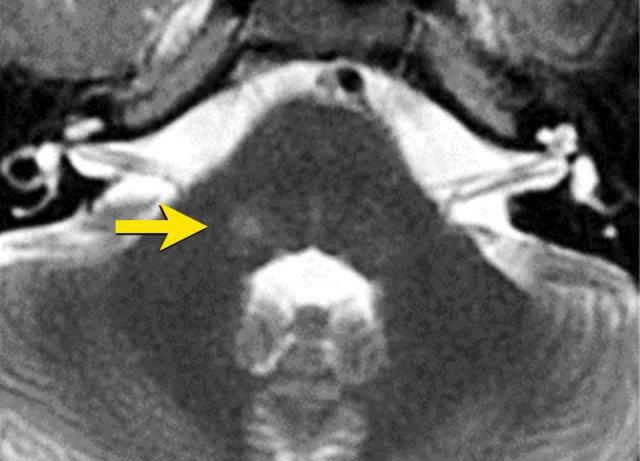

Bệnh nhân nam 74 tuổi có tiền sử đau kiểu “điện giật 220V” tại vùng lông mày phải, má và hàm dưới.

Các triệu chứng này được khởi phát khi rửa mặt và đánh răng.

Hãy xem lần lượt các ảnh cắt ngang 3D FIESTA và ảnh cắt ngang 3D T1W sau tiêm thuốc tương phản từ. Sau đó tiếp tục đọc.

Cả hai chuỗi ảnh cắt ngang 3D FIESTA và 3D T1W sau tiêm thuốc tương phản từ đều cho thấy:

- Mối liên hệ mật thiết giữa dây thần kinh sinh ba bên phải (mũi tên) và động mạch tiểu não trên (mũi tên đứt nét)

- Vị trí tại vùng vào rễ thần kinh

- Thần kinh và mạch máu chạy vuông góc với nhau

- Thần kinh bị đẩy lệch về phía bên

Các phát hiện này đáp ứng đầy đủ tiêu chí chẩn đoán chèn ép mạch máu-thần kinh.